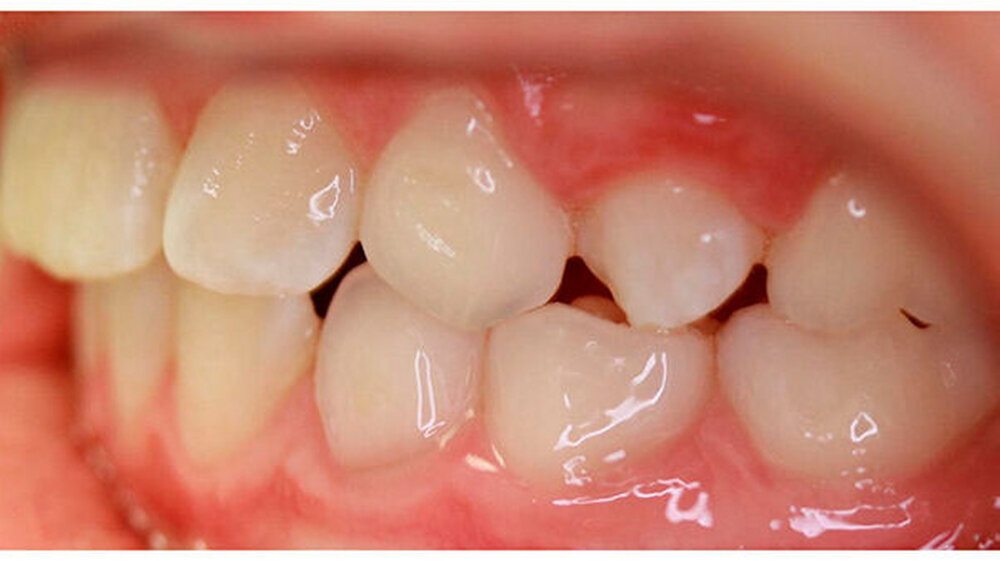

Dieser Fallbericht zeigt eine Patientin mit einer Transposition und multiplen verlagerten Zähnen, die mithilfe eines Gaumenimplantats eingeordnet wurden. Das Mädchen stellte sich im Alter von 13,7 Jahren in unserer Praxis vor. Bei der klinischen Untersuchung fiel die Persistenz mehrerer Milchzähne auf. Der Zahn 13 war distal des Milchzahns 53 durchgebrochen.

Das OPG zeigte eine Dentitio tarda, eine mesial-exzentrische Verlagerung der Zähne 14 und 23 mit Persistenz der Milchzähne 53 und 63 sowie eine Transposition der Zähne 13 und 14. Alle bleibenden Zähne inklusive der Weisheitszähne sind angelegt. Zudem bestand eine mesial-exzentrische Keimlage der Zähne 15 und 25.

Im Rahmen der Modellanalyse ergaben sich folgende Befunde: Im Oberkiefer lagen außer der Transposition der Zähne 13 und 14 multiple Rotationen und Kippstände vor. Die Unterkieferfront wies einen Engstand auf. Im Molarenbereich lag beidseits eine Distalokklusion von ¼ Prämolarenbreite vor. Der Overjet betrug 2 mm, der Overbite 3 mm. Die Zähne 22/33, sowie 24/74 wiesen eine Kopfbissrelation auf.